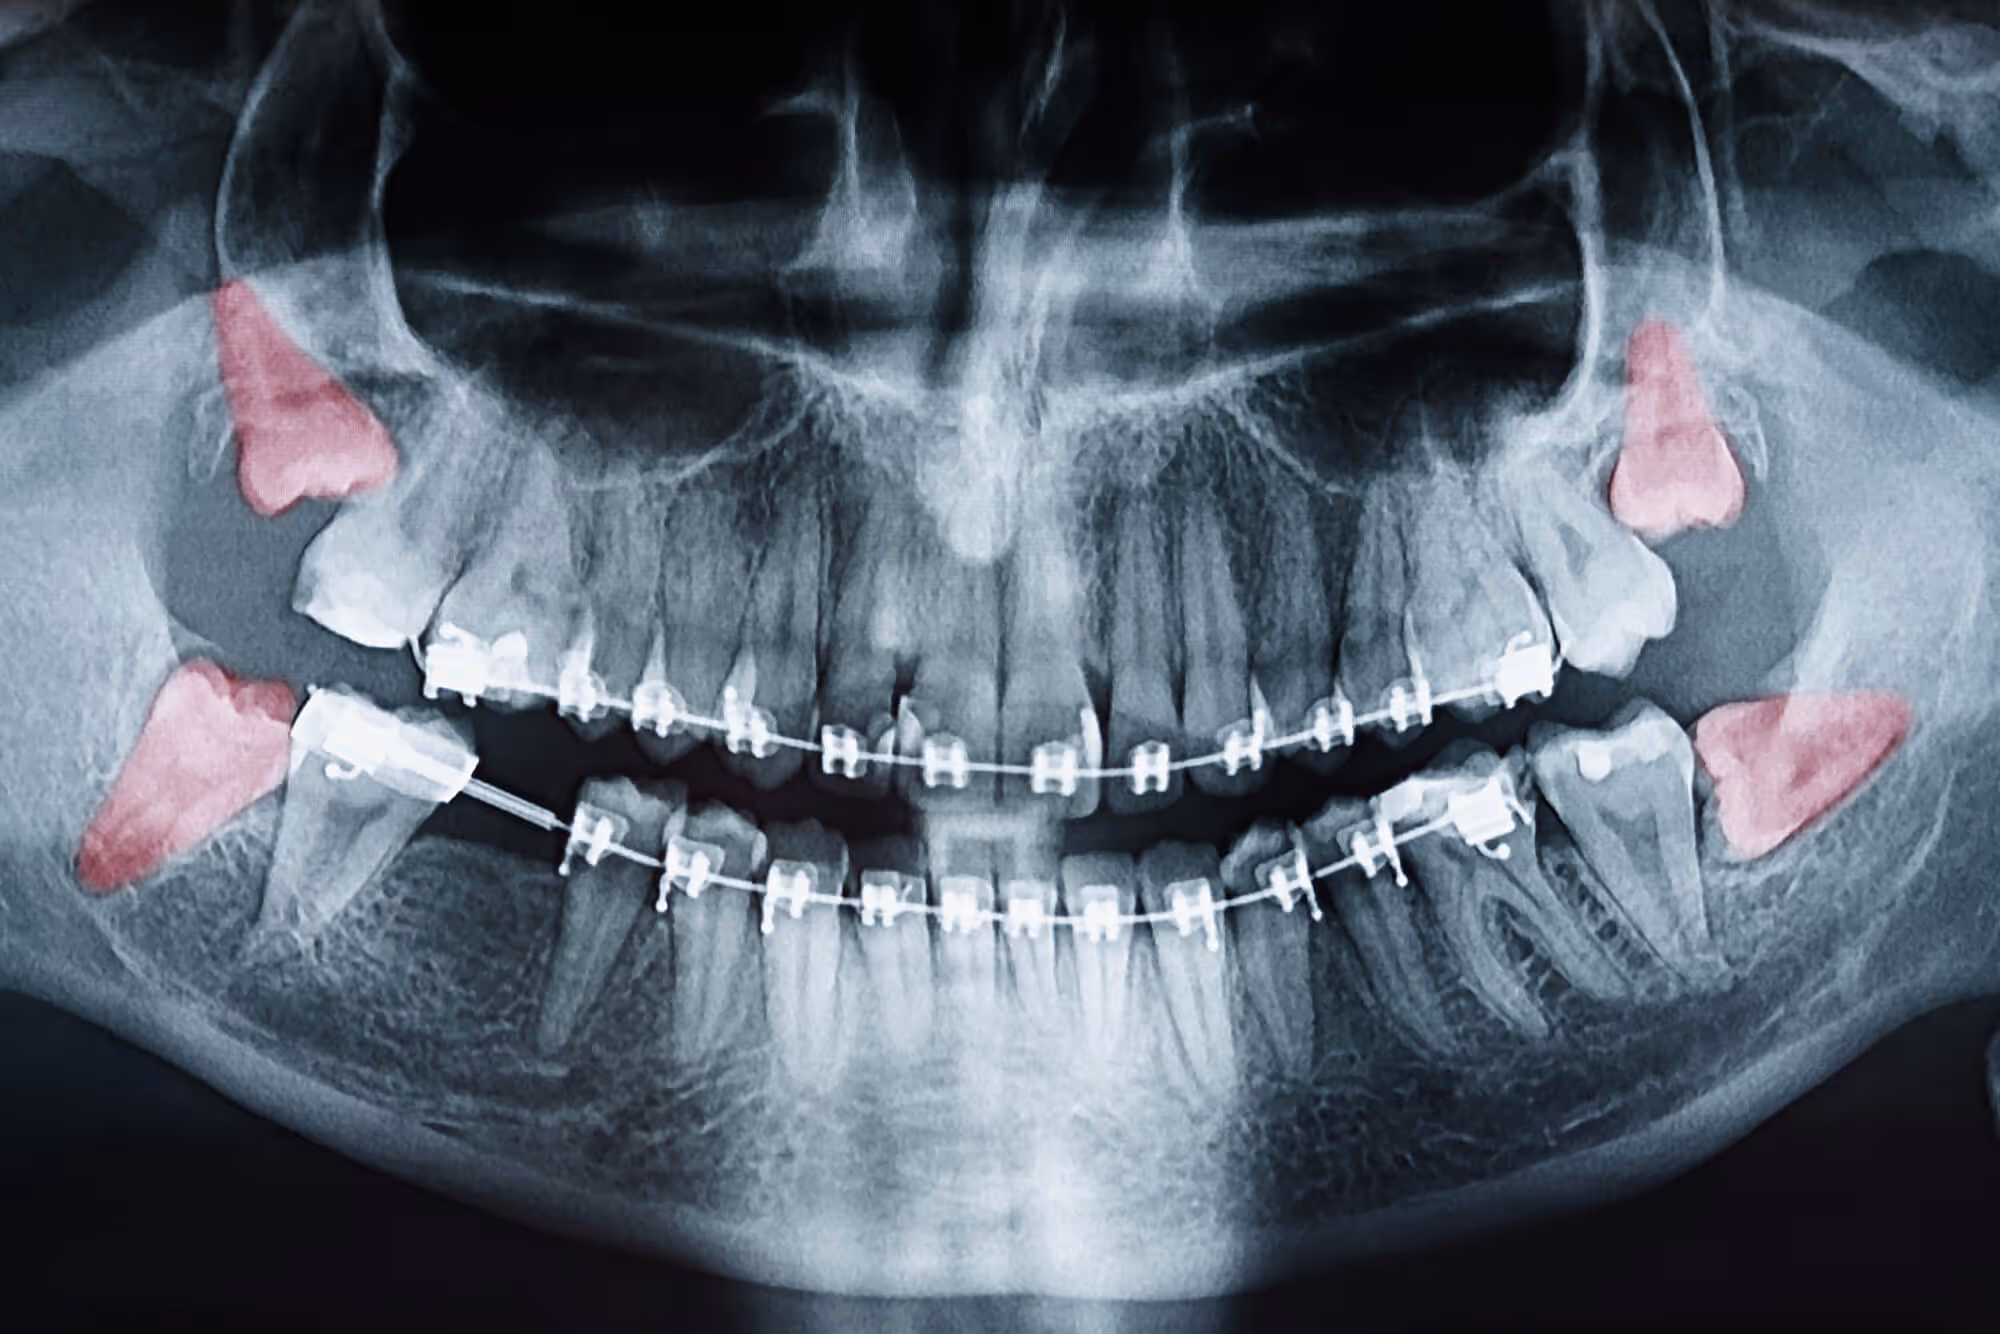

Many patients’ jaws are simply too small to accommodate wisdom teeth. Typically, four of these teeth may come in, and they don’t have room for proper growth. They can also grow in at odd angles, causing them to not erupt from the gums and instead stay under them. Some of them even grow horizontally.

Wisdom teeth become impacted when they can’t rise through the gums. Most people can expect to have at least one of their wisdom teeth to be impacted. Wisdom teeth can put pressure on the other teeth and even on the jaw’s bone. This pressure can be damaging to both, making it smart to remove these teeth before they cause any damage.

The younger the person, the easier the wisdom tooth surgery is. It’s important not to wait a long time to have them out, as the roots of the wisdom teeth will start to curve and grow closer to vital structures such as nerves and sinuses. This can make them less easy to remove. As soon as your dentist recommends that you have your wisdom teeth out, make your appointment to get it done.

If you have been recommended for wisdom teeth extraction surgery, know that it’s a quick, outpatient procedure that is easy for patients. While your general dentist may detect the problem, you will be referred to an oral surgeon for the procedure. You will likely have X-rays taken by your general dentist, and those images will be sent to us for evaluation.